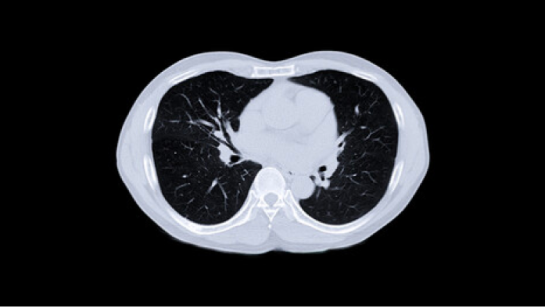

Perform HRCT scan directly

HRCT can provide information on the extent and severity of the disease. For more HRCT related information

For a RA-ILD risk score ≥7, perform high resolution chest CT directly